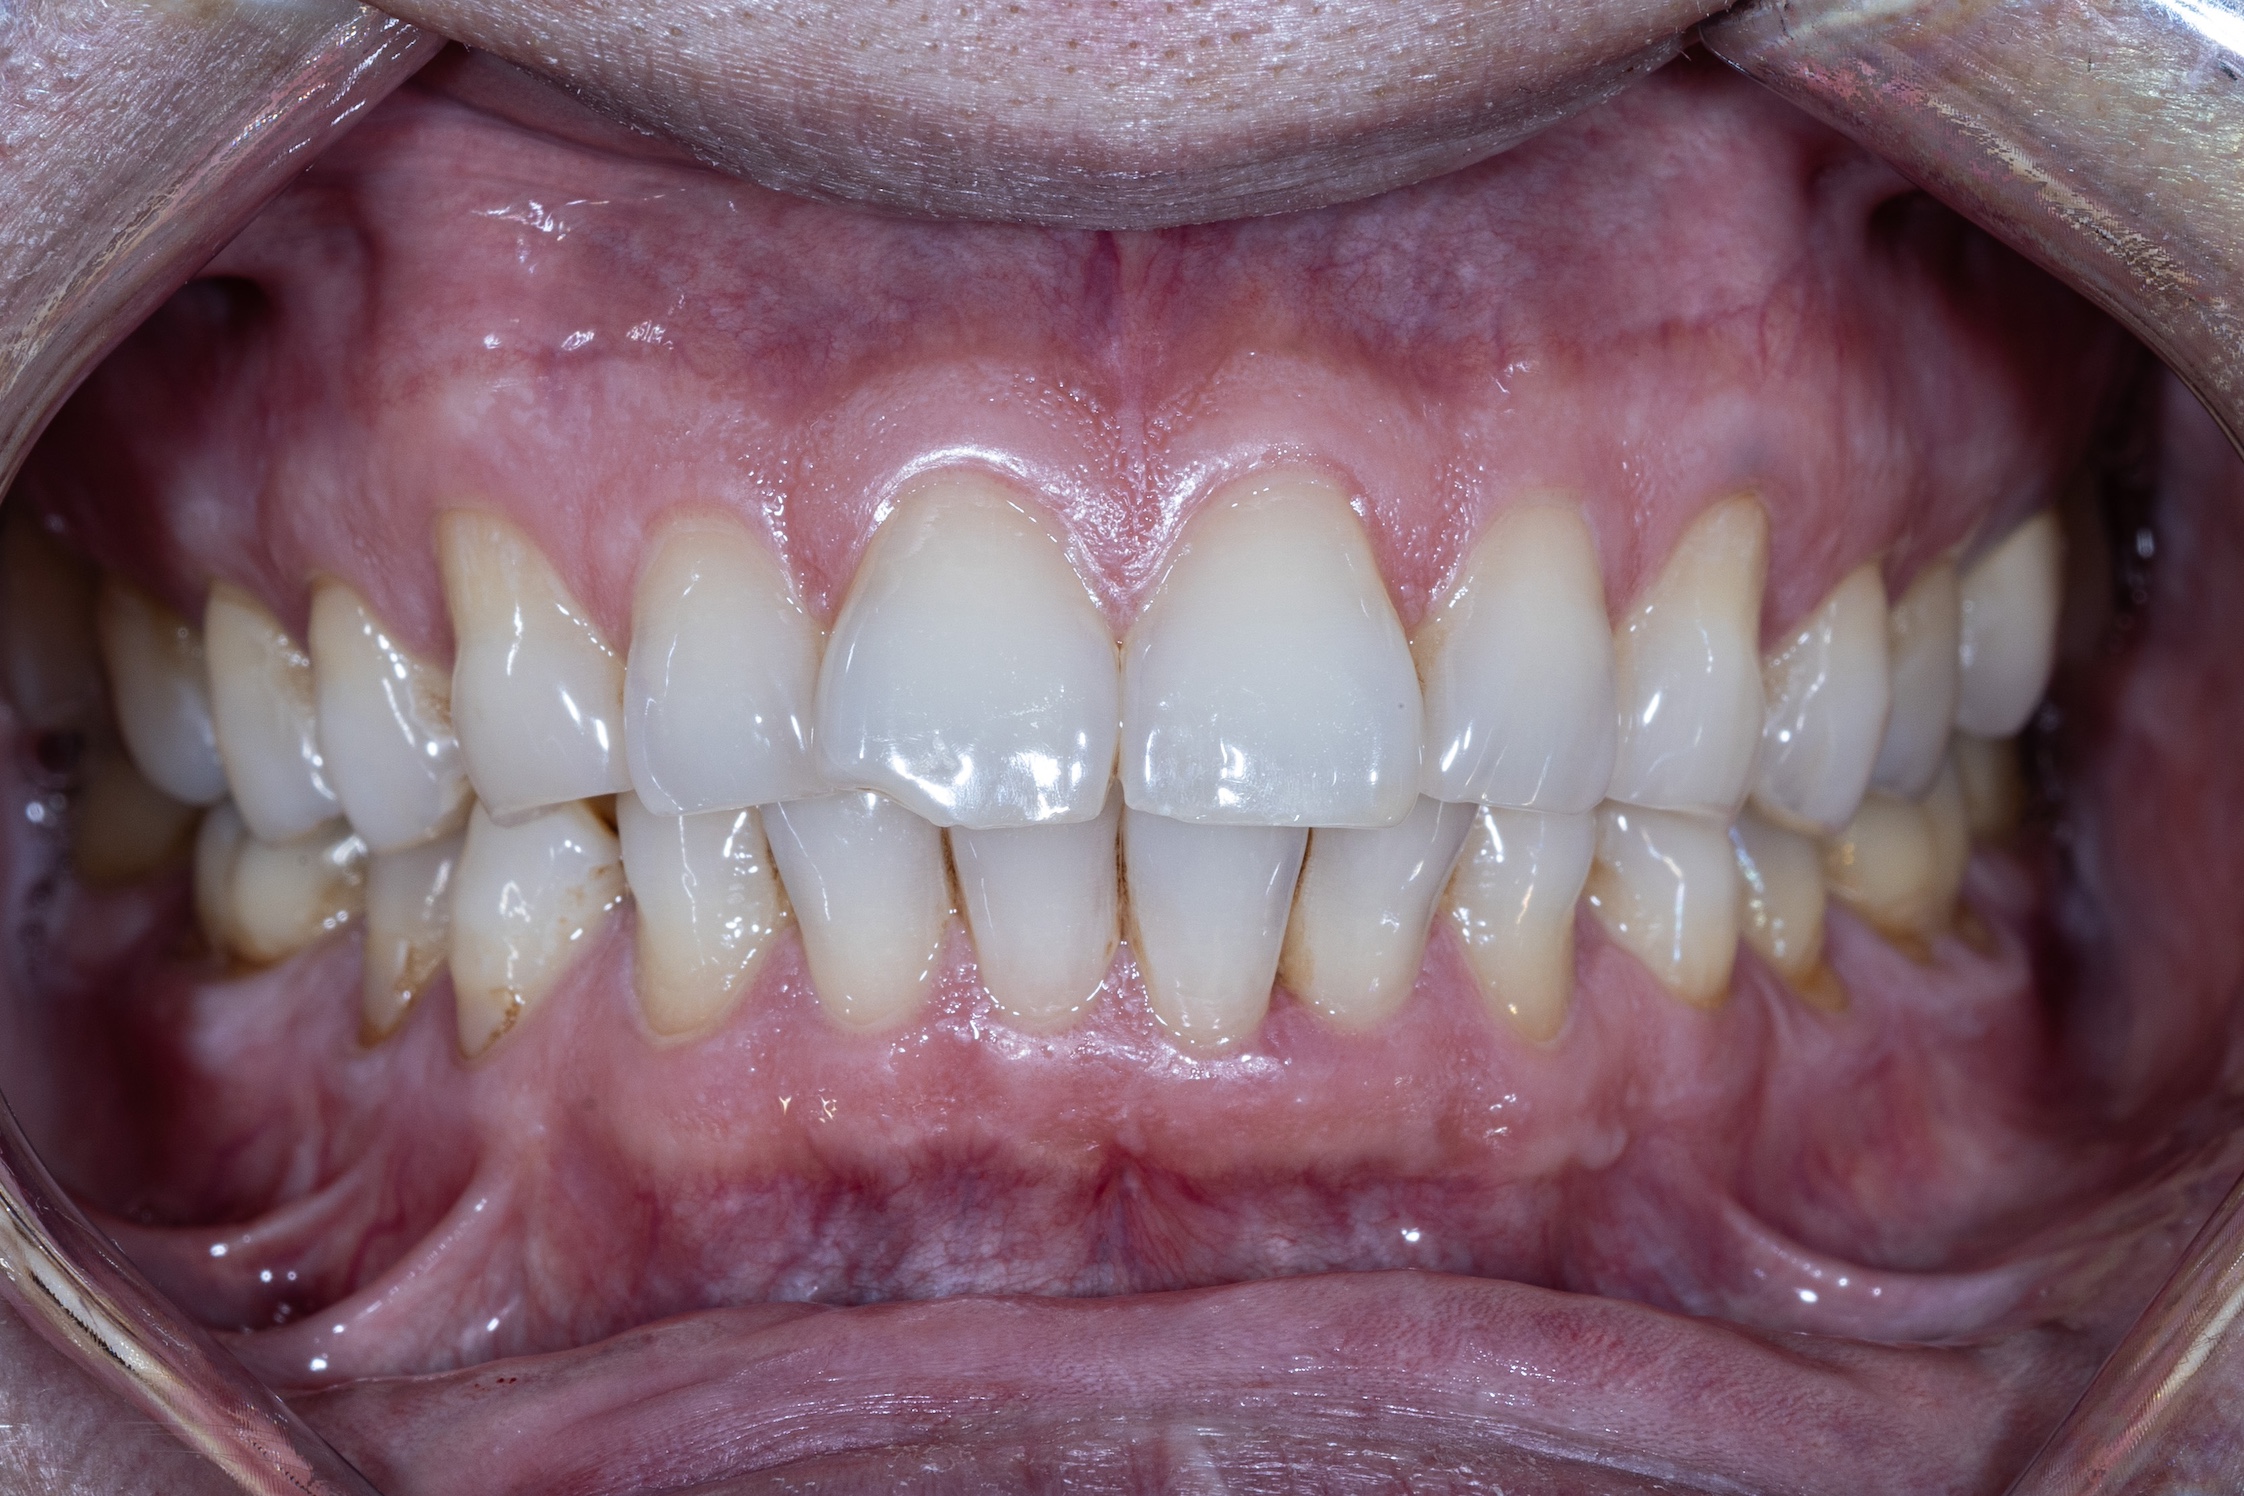

After